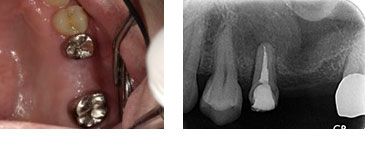

左上6番 抜歯即時インプラント埋入

BEFORE

AFTER

| 金額 | ¥450,000(税抜) |

| 期間 | 約3ヶ月 |

| リスク | オペから6週までは過大な力がかかると骨の2次安定が得られないことがあるため、注意を要する。 |